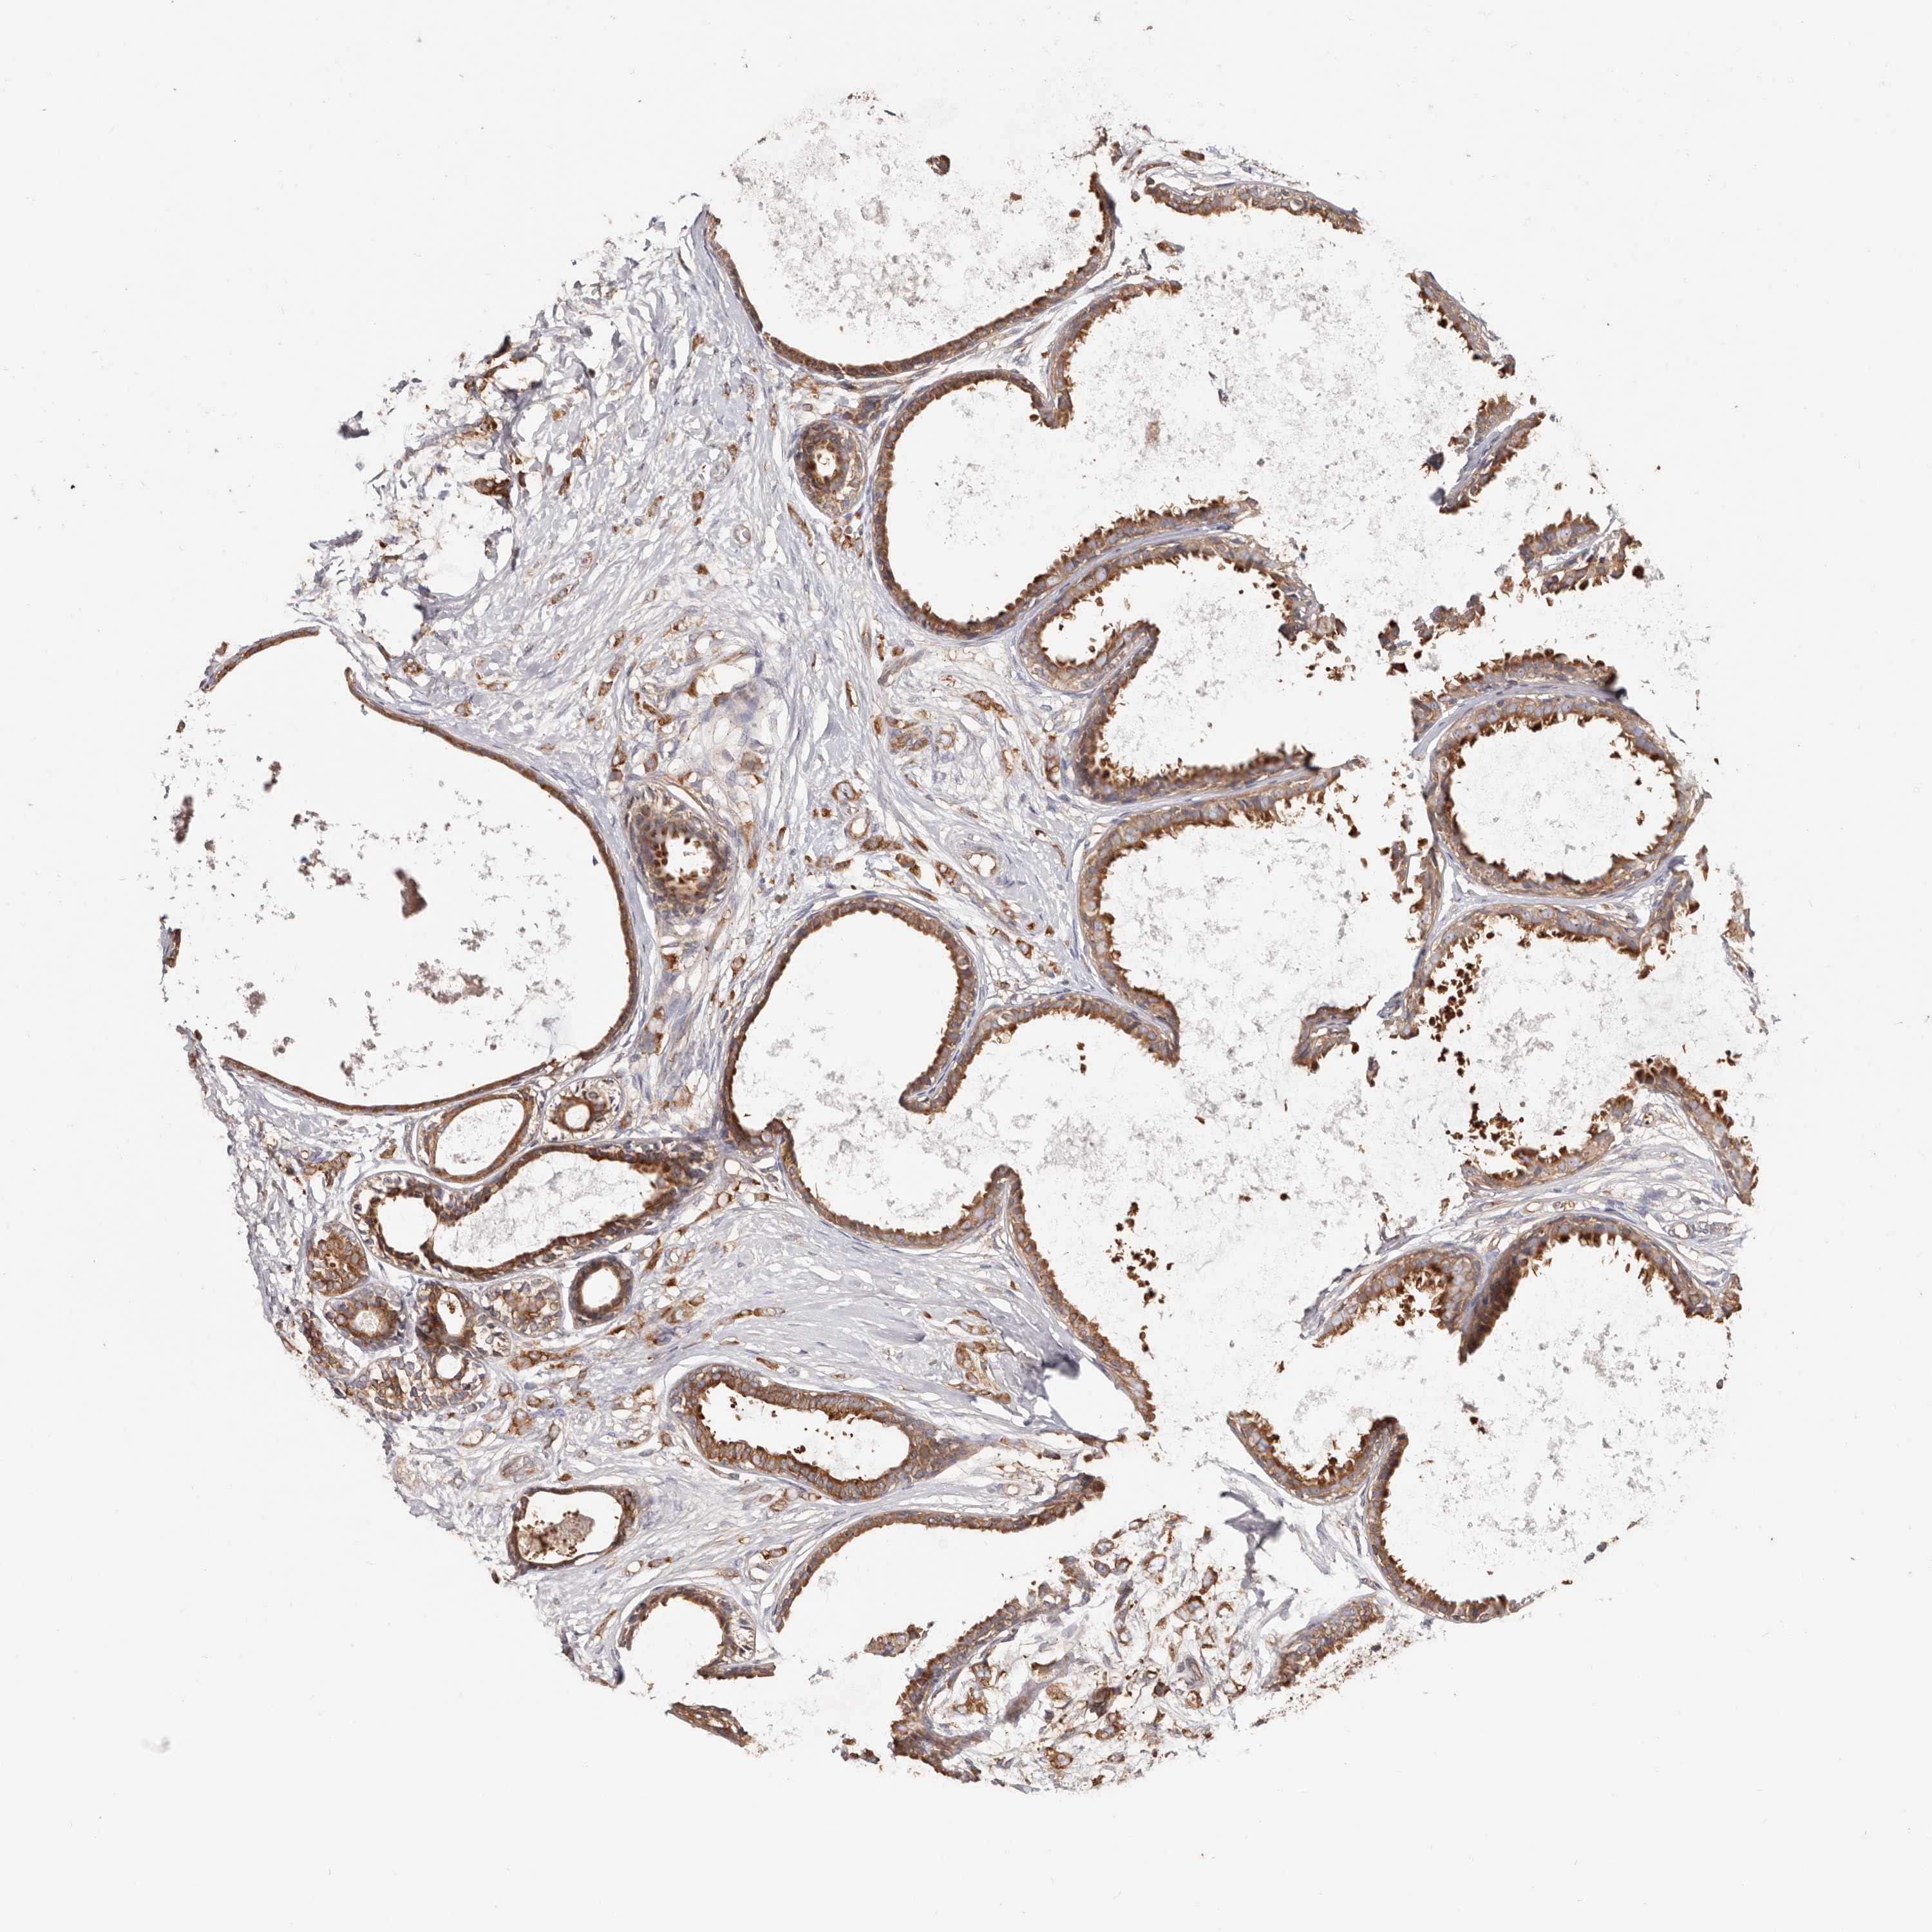

CANCER BREAST CANCER Show tissue menu

BRCA TCGA BRCA VALIDATION PROTEIN EXPRESSION